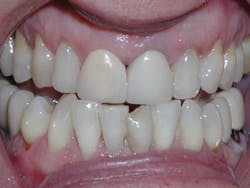

Four weeks later, Evin began his clear aligner treatment (see Figure 1). He was seen for follow-up clear aligner visits at six-week intervals until his treatment was completed. During his clear aligner treatment, Evin maintained three-month recalls with the hygienist. His home care was excellent, in part due to the benefit of aligners being removable.

Figure 1

The six-week follow-up visits with Evin were eye-opening! I had the opportunity to observe his periodontal condition improve at each interval. After 30 aligners, or 15 short months, Evin's clear aligner orthodontic treatment was completed and final photos were taken. His bite was checked to confirm we had achieved our initial goal. Evin now had the appropriate overbite, overjet, and class I occlusion with proper posterior intercuspation with no interferences.

Evin is a perfect example of this. He always had beautiful teeth. Dr. Miraglia could see that they were just in the wrong place! Insufficient space, as a result of improper arch forms is the cause of crowding, not "crooked" teeth (see Figure 1).